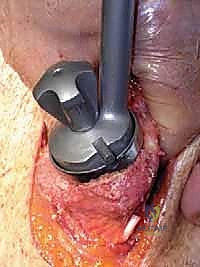

Additional Intraoperative Imaging & Surgical Steps